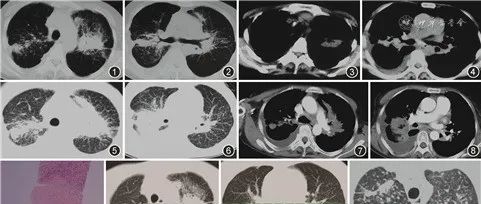

肺结节病伴胸腔积液三例

本文原载于中华结核和呼吸杂志, 2021,44(4) : 380-382. DOI: 10.3760/cma.j.cn112147-20210120-00060例1 女,51岁。2016年12月因“间断咳嗽伴胸闷2年”于当地医院行胸部CT(图1, 2, 3, 4),提示双肺弥漫性病变伴右侧胸腔积液,抗感染治疗无好转。2017年2月转诊至上级医院住院,行血常规、肝肾功能、ESR、C反应蛋白及肿瘤标志物等检查结果未见异常,结核菌素斑点试验(T-SPOT)阴性。胸腔积液检查:李凡他试验阳性,细胞数为2 600×10...